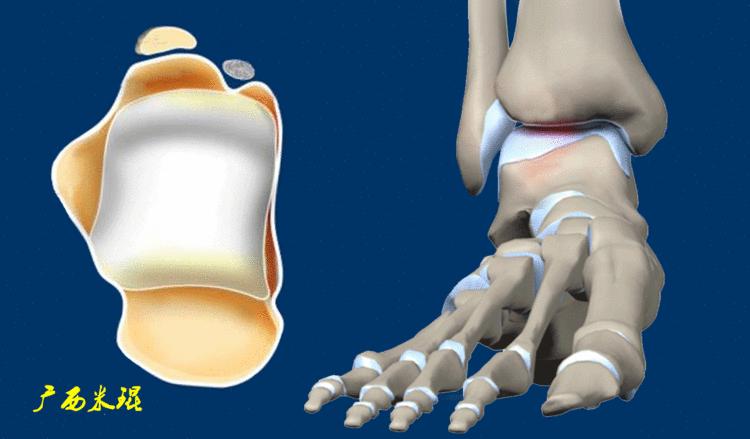

Raikin将距骨骨软骨进行九宫格分区对临床是很有帮助的,距骨骨软骨的后内侧损伤一般发生在4区和7区,前外侧损伤一般发生在3区和6区。除此之外,Raikin九宫格分区对手术也有很大帮助,4、5、6区的损伤手术显露有一定的困难,如果选择骨软骨移植一般都需要采取截骨显露的方法。